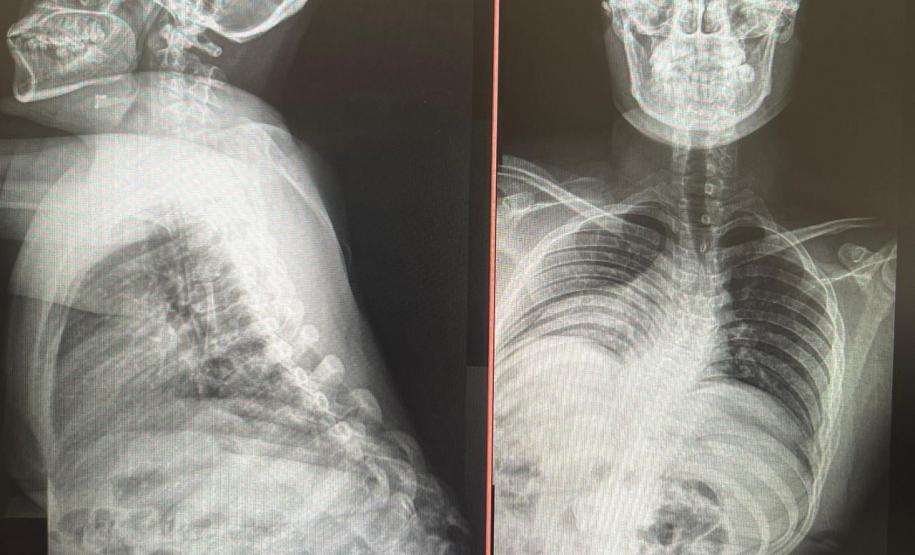

Aos 14 anos, a adolescente Milena de Andrade Carvalho, moradora de Guaratuba, no Litoral do Estado, foi diagnosticada com escoliose idiopática. Sem causa definida, esse tipo de escoliose pode surgir a partir dos quatro anos até a adolescência e ocorre durante o estirão de crescimento. Quando a condição da curvatura ultrapassa os 40 graus, a escoliose se torna progressiva e o paciente continua entortando. Essa condição ocorre com maior frequência em meninas e é muito importante que os pais estejam atentos a qualquer sinal do problema.

“Descobrimos a escoliose por acaso, nunca tínhamos percebido a deformidade, até que um dia ao amarrar meu biquíni, minha mãe observou que eu estava com a coluna torta e ao passar a mão percebeu a curvatura. Decidimos então procurar atendimento médico e tive o diagnóstico da doença já com 50 graus de curvatura e indicação imediata de cirurgia”, contou a adolescente.